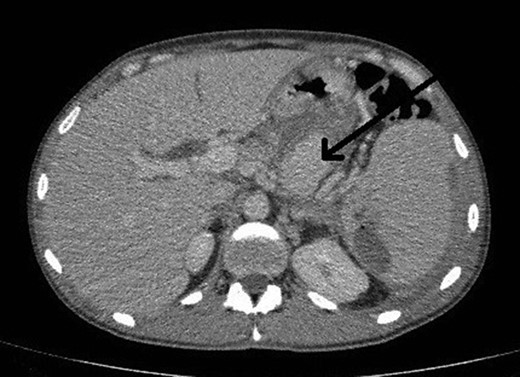

However, 4 days after the ultrasound guided injection, the patient collapsed on the ward with haematemesis and hypovolaemic shock. He was resuscitated initially with intravenous fluids and transfusion of blood products and remained alert with no abdominal signs. An emergency gastroscopy showed a 1.5 cm gastric ulcer on the posterior gastric wall with a large clot in the upper stomach but no active bleeding. A repeat CT abdomen demonstrated persistent flow in the pseudoaneurysm (Fig. 4).

CT abdomen image post thrombin injection shows flow in the pseudoaneurysm (arrow).